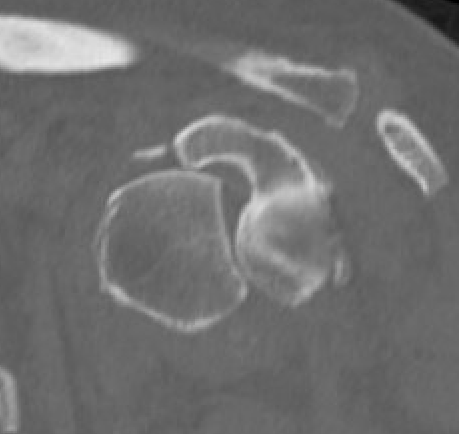

CT

Assess bone stock / glenoid bone loss / Hill Sachs lesions

Chronic shoulder dislocation with large Hill Sachs and minimal glenoid deficiency

Chronic shoulder dislocation with large Hill Sachs and significant glenoid deficiency